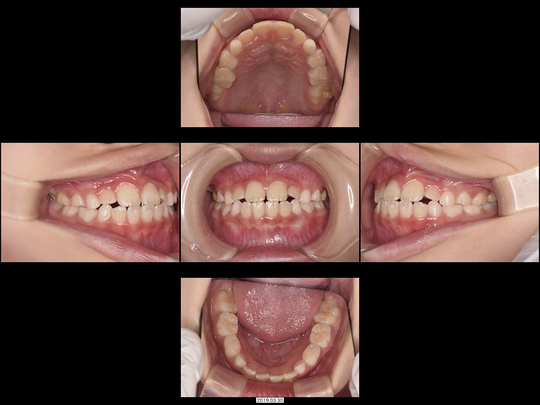

Aさん 開始時6歳 女性

矯正前

歯列矯正用咬合誘導装置(ムーシールド)  開始

画像をクリックで拡大